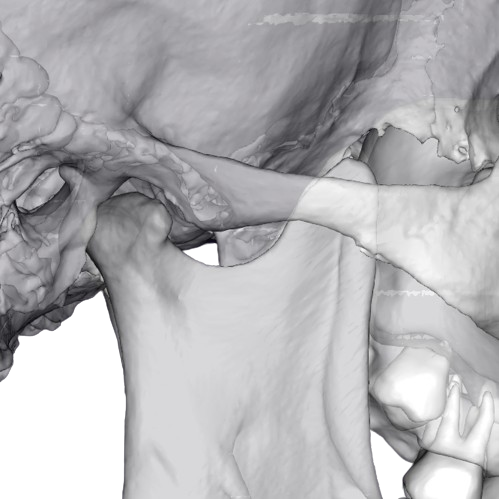

Об’єм: 16×8 см

1200 ₴

Призначається для виявлення дегенеративно-дистрофічних і деструктивних змін на різних стадіях.

Записатися Детальніше

Об’єм: 16×8 см

1000 ₴

Призначається для виявлення дегенеративно-дистрофічних і деструктивних змін на різних стадіях.

Записатися Детальніше